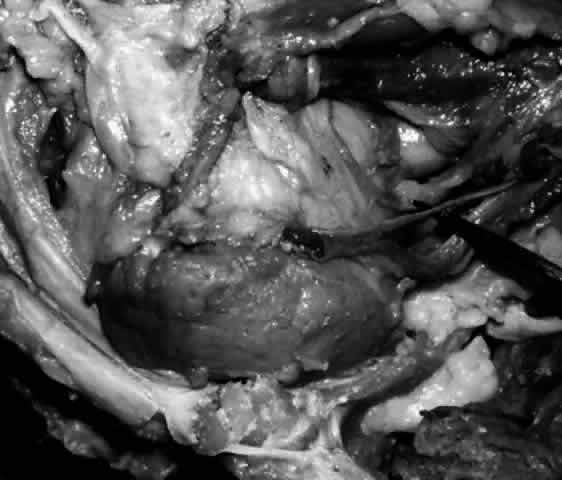

Lacrimal Sac

The lacrimal sac and the nasolacrimal duct form one continuous structure (Fig. 20). The uppermost portion lies within the bony lacrimal sac fossa and is termed the lacrimal sac. The middle part is contained within an osseous channel in the maxilla and is termed the nasolacrimal duct. The inferior-most portion of the nasolacrimal duct courses for a short distance beneath the nasal mucosa of the lateral wall of the inferior meatus and is therefore known as the meatal portion. Individual variations in the membranous lacrimal sac and nasolacrimal duct are due to variations in the surrounding bony configuration.2

Fig. 20. Skeletonized right lacrimal excretory system. With the bony canal removed, the lacrimal sac (small arrow) is seen in continuum with the nasolacrimal duct (large arrow). The pointer is behind the upper and lower canaliculi.

The lacrimal sac is approximately 12 mm in height, 4 to 6 mm in depth, and 2 mm wide. The 4-mm portion of the sac that projects above the medial canthal tendon is somewhat pointed and is termed the fundus (Fig. 21). The larger portion below is termed the body. The walls of the sac are in apposition, unless the sac is filled with lacrimal fluid. The sac is somewhat larger in male subjects.19,21